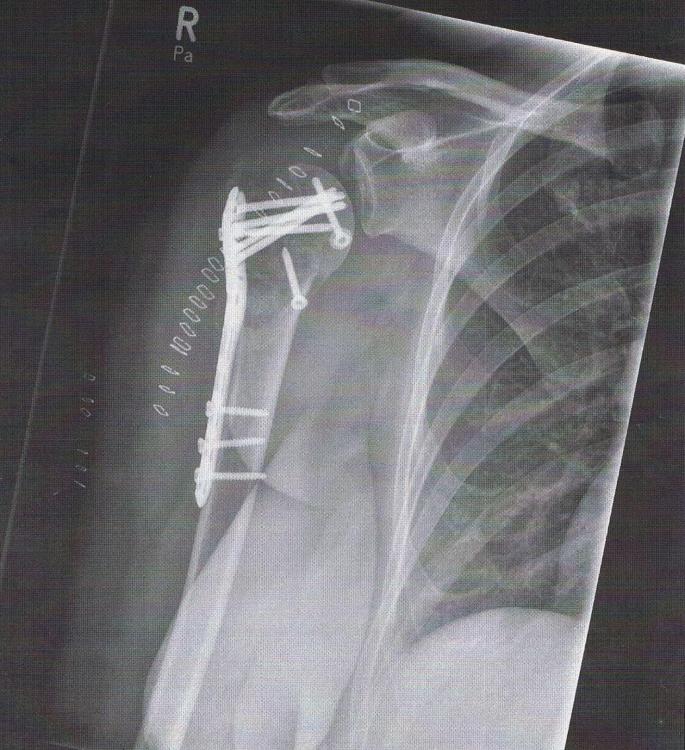

2. Hallo Cianni, vielen lieben Dank für Deine Zeit, die Du Dir für mich genommen hast. Gestern habe ich ganz viel im www gelesen und nach Ärzten gesucht, die sich mit dem Thema Schulter seit Jahren beschäftigen. Ich habe auch schon einen Termin bekommen, aber erst am 1.8.2019. Besser, als gar keinen Termin. Ich bin noch immer positiv denkend (manchmal habe ich auch so Tiefs, wie am Tag, als ich meinen Post hier ins Forum gesetzt habe) und kämpfe, dass ich mich irgendwann wieder gut bewegen kann. Dazu gehört Geduld, ich weiss, aber das ist nicht meine Stärke. Die letzten Röntgenaufnahmen zeigten, dass der Humeruskopf, sagen wir mal, dass Stück, was noch vorhanden ist, gut durchblutet wird. Das habe ich Gott sei Dank geschafft oder kann sich das noch verändern? Nach meinem Unfall habe ich auch sofort mit dem Rauchen aufgehört und glaube, dass ohne das Rauchen die Durchblutung besser funktioniert. Ein Gutes hatte ja der Unfall.... Die RV werde ich nach Pfingsten anrufen und hinterfragen, wo das Problem liegt, dass es so lange dauert. Zum Thema Osteoporose kann ich sagen, dass ich keine habe laut den Untersuchungsergebnissen. Ich werde mich wieder melden und bedanke mich nochmals sehr. Liebe Grüße und ein schönes Pfingstfest Constanze P.S. Hier ist noch ein Foto von mir bzw. meiner rechten Schulter

3. Guten Tag, ich bin ein kleiner Pechvogel. Am 28.01..2019 erlitt ich durch einen Sturz bei Glatteis eine dislozierte mehrfragmentäre proximale Humerusfraktur rechts mit subcapitaler Fraktur und Beteiligung von Tub. majus und minus. Die erste Operation war dann am 01.02.2019 (offene Reposition, Schrauben- und winkelstabile Plattenostensynthe (Synthes Philos 3.5, 5-Loch-Platte), Defektauffüllung mit allogener Spongiosa, Anschlingung der Rotatorenmanschette an Platte.......... Befund vor Operation: Röntgen Oberarm in 2 Ebenen und Röntgen Schulter in 2 Ebenen Bild einer capitalen und subcapitalen Humerusfraktur rechts mit multiplen trümmerförmig ausgesprengen dislozierten Fragmenten cranial, ventral und dorsal des Humeruskopfes und metaphysär gelegen. Ausgesprengtes Tuberculum majus und minus. Die Humeruskopfcalotta ist nach craniodorsal rotiert. Röntgen nach der 1. OP: Z.n. operativer Versorgung der proximalen mehrfragm. Humerusfraktur r. mit Fixation des Kopffragmentes durch winkelstabile Platte und Schraubenrefixation des großen tu.-minus-Fragmentes. bis auf verbliebene Dehiszenz des anterioren Fragmentes achsgerechte Stellung der Fragmente, regelrechte Implantatlage ohne Hinweis für artikulären Schraubenüberstand. Verlauf: Aufgrund der massiven Schwellung der rechten Schulter war eine sofortige operativer Versorgung nicht möglich. Hinsichtlich der Art der Versorgung sahen wir in Anbetracht des Alters der Patientin (50 J.) einen Erhaltungsversuch des Humeruskopfes für gerechtfertigt an, klärten die Patientin jedoch über die Chancen und Risiken, insbesondere die Möglichkeit einer ausbleibenden knöchernen Heilung oder eines Absterbens des Humeruskopfes und der dann notwendigen Implantation einer Schultergelenksendoprothese ausführlich auf. Mit meiner Entlassung am 8.2.2019 wurde bis zur 2. OP nur Lymphdrainage verordnet, keine Bewegungsübungen. Die 2. Operation wurde am 29.4.2019 durchgeführt mit vorheriger Diagnose Intraartikuläre Fragmente rechtes Schultergelenk und Schraubenüberstand bei dislozierter mehrfragmentärer proximaler Humerusfraktur rechts Empfehlung: aktive Bewegungsübungen bis 5 kg Last über die nächstenm 4 Wochen.... Verlaufskontrolle nach 3 Monaten mit Bildgebung....Materialentfernung und ggf. Arthrolyse ist nicht vor einem Jahr nach Osteosynthese zu erwarten. Jetzt zu meinem jetzigen Problem: Ich habe seit ca 3 Wochen Bewegungsübungen in einer physiotherapeutischen Praxis. Termin sind hier nur 1x oder 2x die Woche möglich gewesen. Es wurde vorher nur Lymphdrainage gemacht, da mein ganzer Arm noch geschwollen war und starke Schmerzen bestanden und noch bestehen. Den Arm bekomme ich nicht von alleine gehoben. Ich habe ein elektrisches Hilfsmittel für die Abduktion für zuhause bekommen. Dort bewege ich zur Zeit den Arm bis 59 Grad, mehr geht noch nicht. Ich übe auch alleine mit Pendeln, damit die Schulter bewegt wird. Seit Montag habe ich die Physiotherapie gewechselt. Jetzt sind 3x die Woche für Bewegungsübungen eingeplant. Eine Reha habe ich seit 3 Wochen beantragt, noch keine Nachricht bisher vom Rententräger erhalten. Dadurch, dass ich auch ohne Bewegung meist starke Schmerzen habe, weiss ich im Moment nicht mehr ein noch aus. Mein behandelnder Chirurg ist kein Schulterspezialist, versorgt mich jedoch mit Physio und Schmerzmittel. Bei meinem letzten Besuch bei ihm empfahl er mir dringend eine Zweitmeinung bei einem Spezialisten einzuholen. Er könne mir nicht helfen. Ich habe im Internet recherchiert und gesucht. Irgendwie komme ich mir so allein und hilflos im Moment vor, weil mir selbst der Arzt nicht helfen kann. Ich möchte doch wieder so gerne mich bewegen können, mal wieder Auto fahren können oder am PC nicht nur mit der linken Hand tippen müssen.......Kann mir hier im Forum jemand helfen, indem er mir richtige Physiotherapie benennt oder mir einen Spezialisten empfehlen kann- Ich habe schon über eine Schultergelenksendoprothese nachgedacht...... Liebe Grüße Constanze